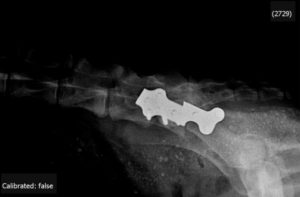

• radios fournies : subluxation coxofémorale bilatérale

• pas de coxarthrose notable

• radiographie pelvienne de face en position DCF et de recentrage :

• dysplasie coxofémorale stade D avec forte subluxation

• tête fémorale de petit volume

• pas de pathologie dégénérative articulaire majeure détectable

• angle de Norberg-Olson < 105° bilatéral

• profondeur cavités acétabulaires satisfaisante

• recouvrement tête fémorale attendu correct

• synthèse par plaque Chancrin angulée à 30° – 2 vis 3,5 mm autotaraudantes  6 vis spongieuses en 4mm

contrôle radiologique post-opératoire : le recouvrement acétabulaire n’est pas majeur à ce stade – il devrait progresser dans les 45 jours post-opératoires – il sera à ré-évaluer radiologiquement régulièrement